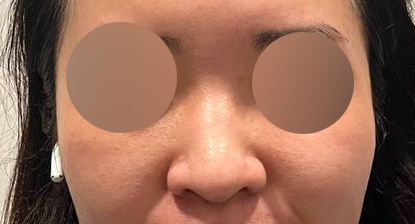

코성형 1개월차 찐 후기:)

1개월차 찐 후기 올려요 :)

지금 제 코는 만족스러우며 아직 한달지만

주마다 코 모양이 달라지는걸 느끼고 있습니다!

유영문 원장님이 아주 잘됬다며 칭찬해주실때마다

더 이뻐지길 기대하고 있어용 ㅎㅎㅎㅎ